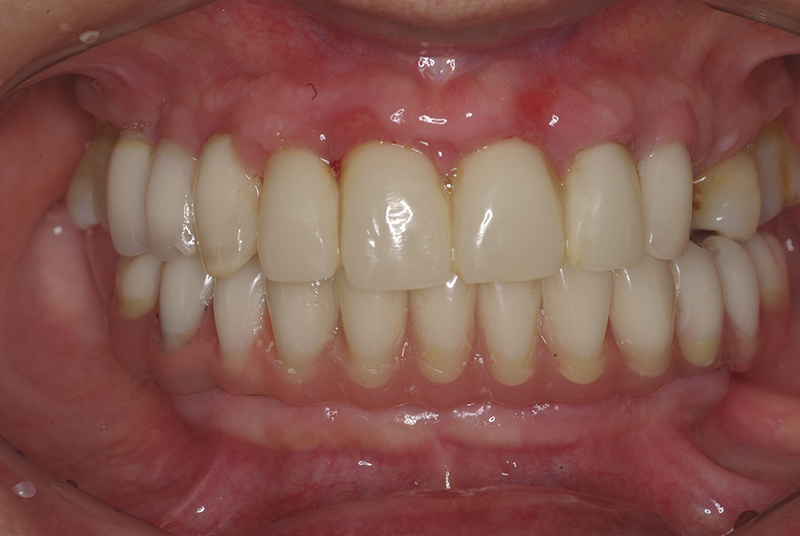

- Conforto e Estética: A prótese provisória é funcional e visualmente semelhante aos dentes naturais.

- Melhora da autoestima: O impacto positivo de um sorriso completo é imediato, melhorando a qualidade de vida.